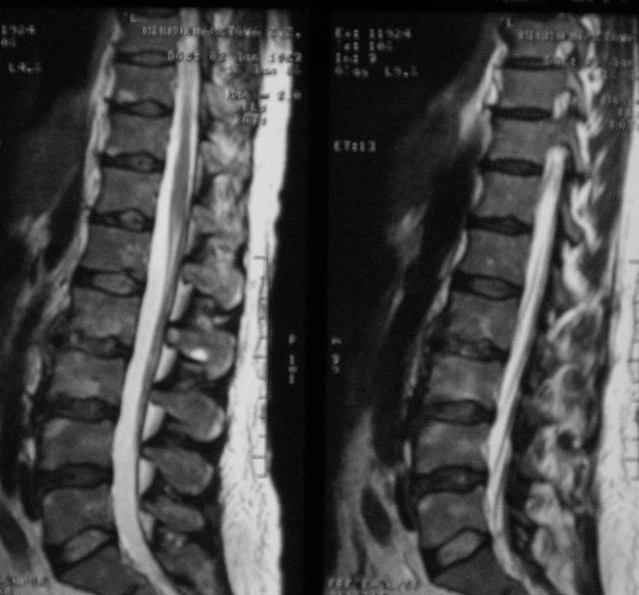

Отправляю MRI в динамике, снятые с пленки на фотоаппарат.

|

MRI через три недели

По данным представленных КТ и МРТ у больной имеется достаточно выраженная степень деструкции тел позвонков (около 30% общей костной массы тела позвонка), что определяет высокий риск возникновения патогических переломов и появления локальной кифотической деформации на этом уровне.

Уважаемый доктор! судя по последнему МРТ процесс затрагивает соседние позвонки с переходом процесса через диск. Для туберкулёза как раз и характерна картинка "целующихся" позвонков. При бактериальном процессе диск страдает лишь вторично. Туберкулиновые пробы могут быть в пределах нормы, лёгкие - чистые. Вообще туберкулёз последнее время стал очень коварен и атипичен. Такие случаи отмечались у детей старшего возраста.

Данные МРТ выкладываешь некорректно - это не "контроль в динамике", а поход по Сусанинским местам, сравниваемые срезы за разные даты должны быть одинаковыми.